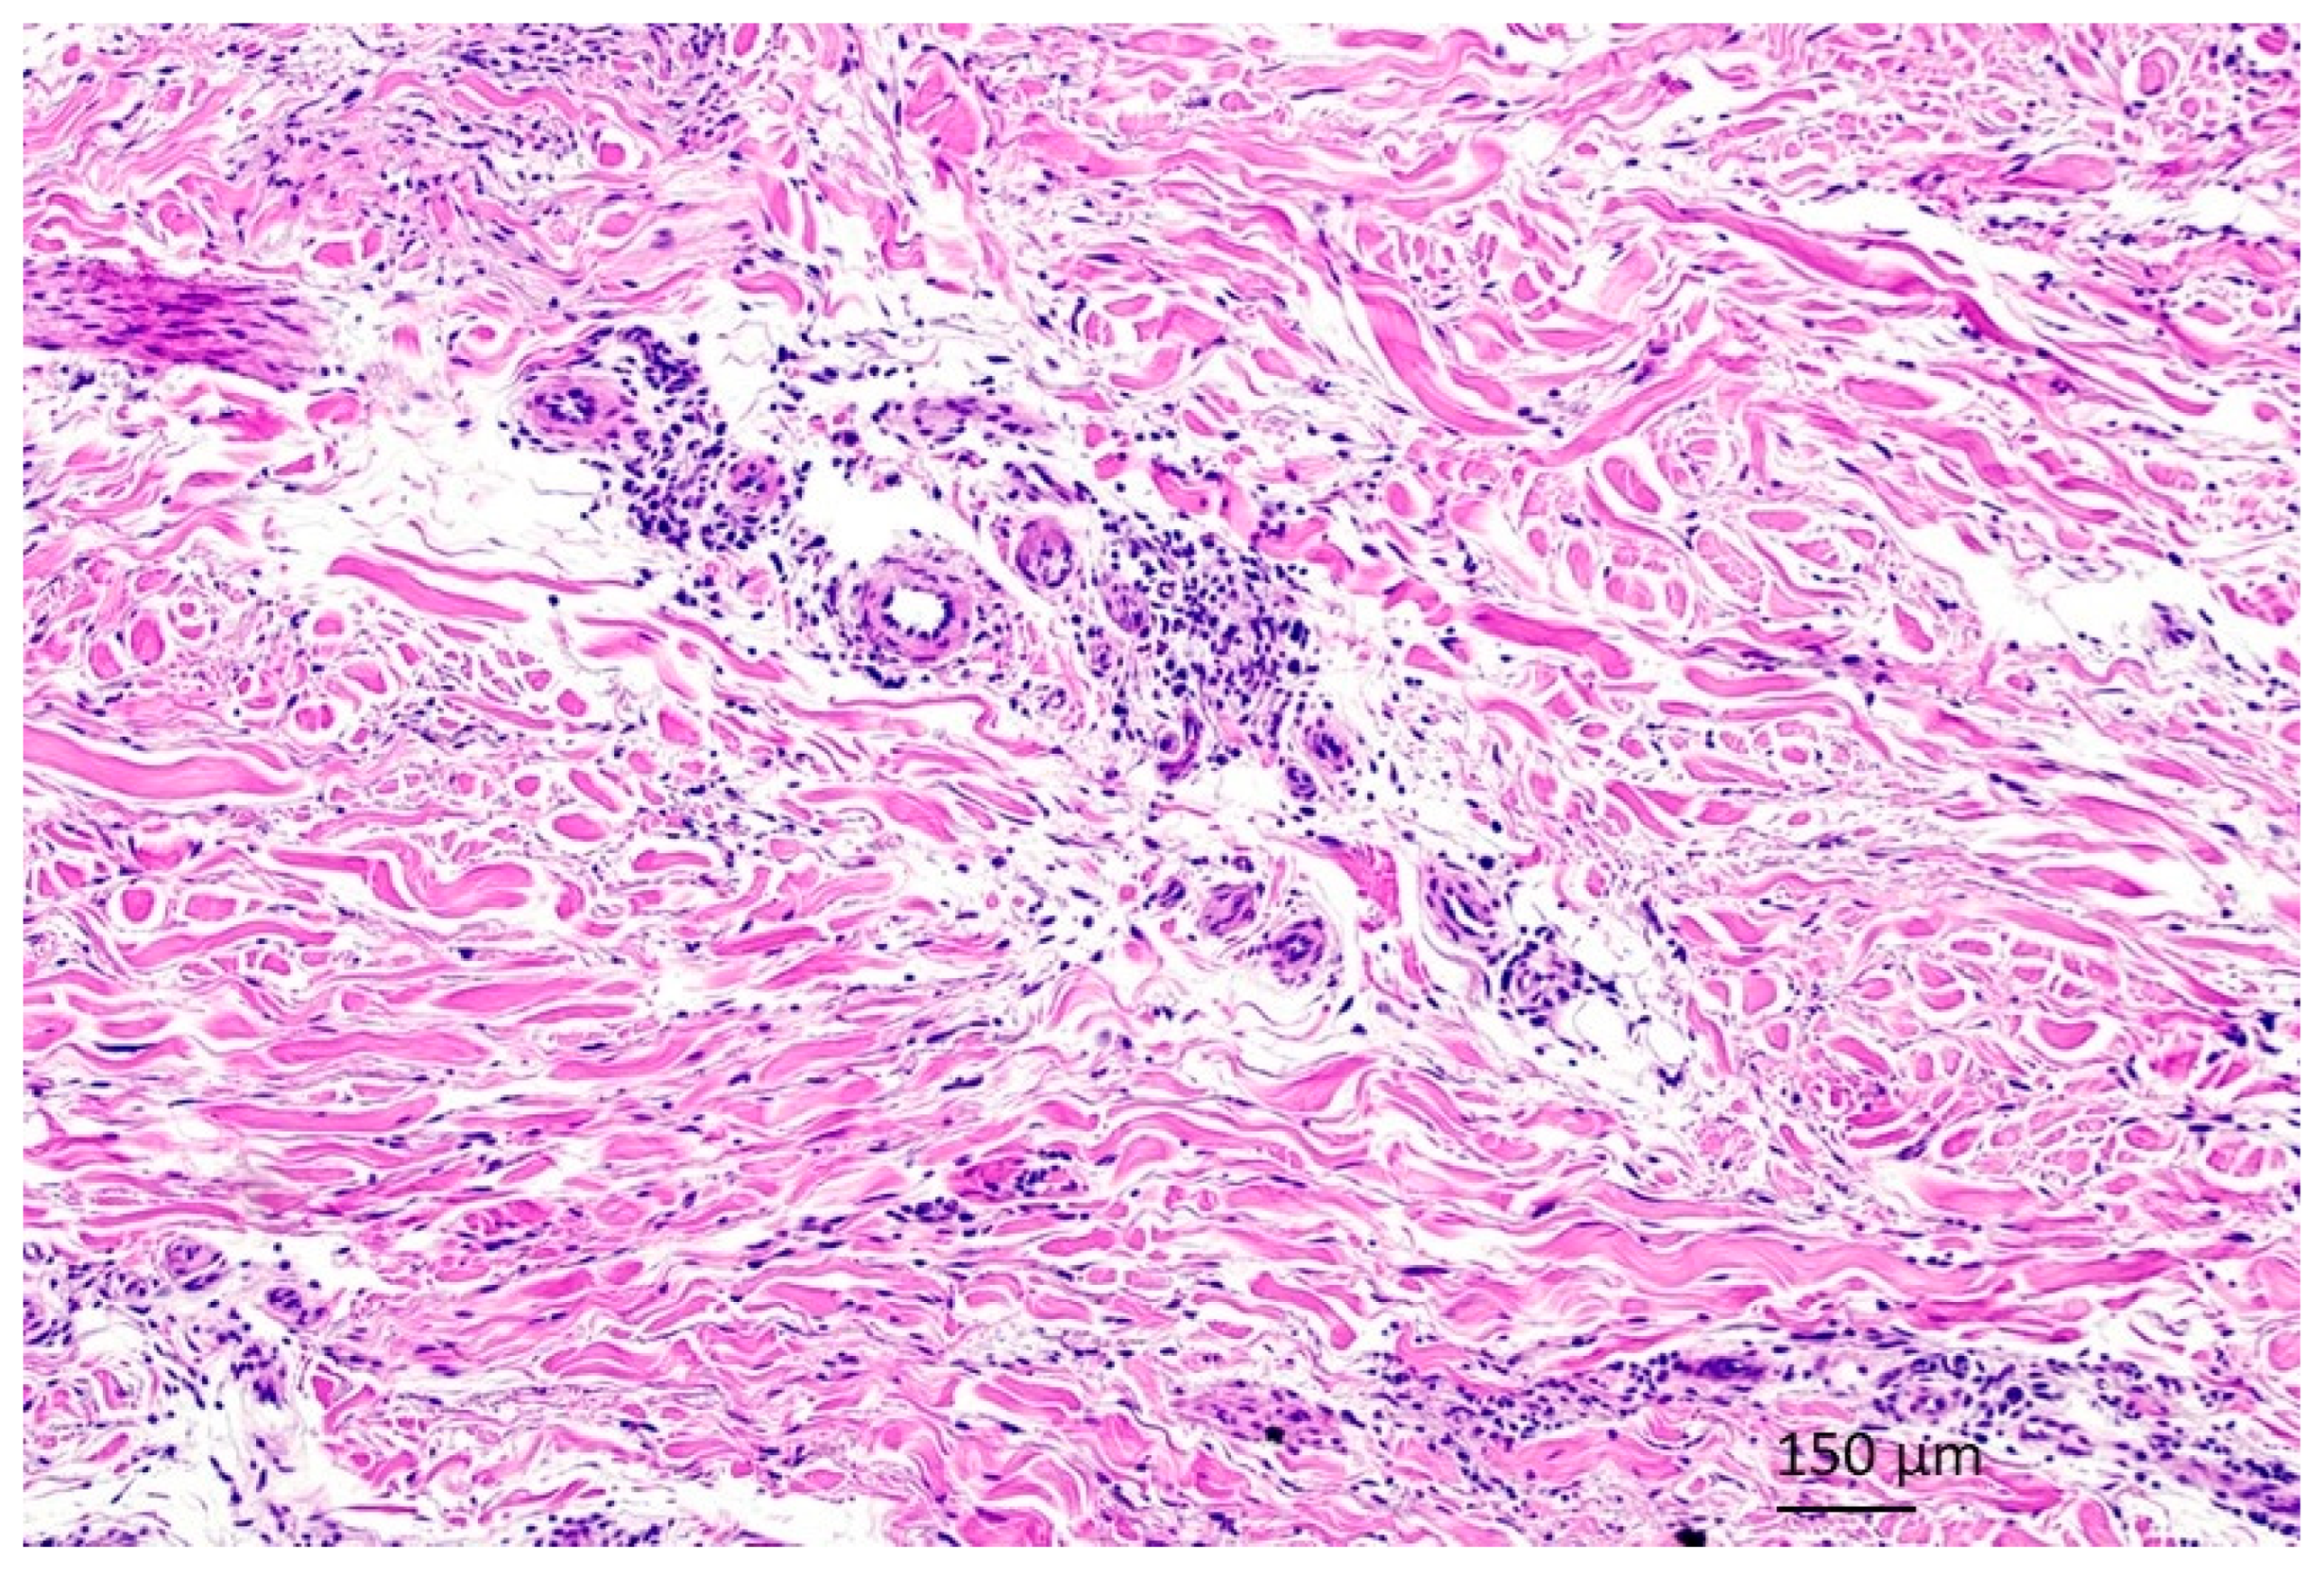

1. Introduction

2. Case Presentations

2.1. Case 1

2.2. Case 2

2.3. Case 3

3. Discussion